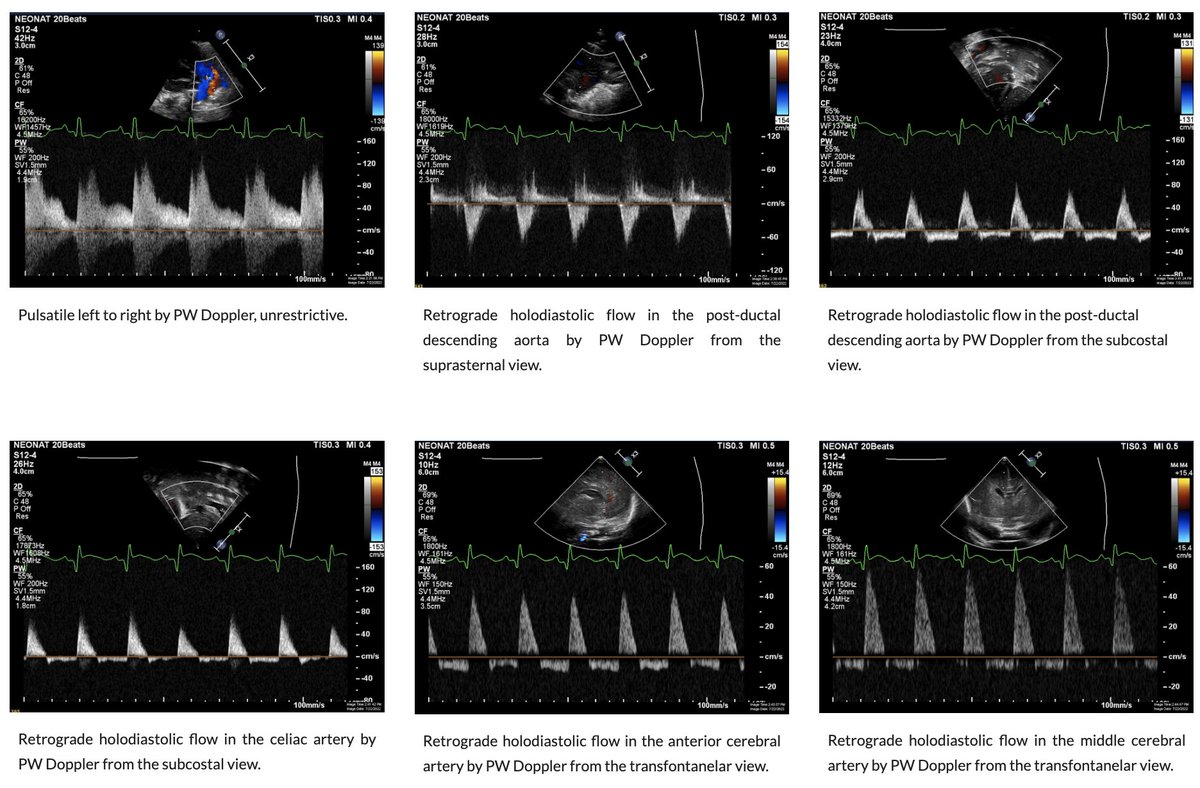

Some Echo-Doppler signs of ductal systemic steal from the systemic to the pulmonary circulation. Here, in the case of extreme prematurity. Read/see more on NeoCardioLab PDA section neocardiolab.com/tnecho_1/paten… Scottish Neonatal Haemodynamics & POCUS Group NicuPocus Neonatal Hemodynamics Research Centre Neonatal Heart Society Audrey Hebert